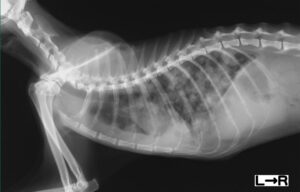

その他に、転移の確認のためレントゲン検査もしくはCT検査などによる画像検査も行います。

もし、左右の両側に乳腺腫瘍がある場合は、一度の手術で両側乳腺全摘出をせず1か月ほどの間隔をあけて片側ずつ広範囲の切除をします。これは乳腺とともに皮膚も広範囲に切除し縫い合わせる影響で、術後に胸が十分に膨らむだけの皮膚の余裕がないために呼吸が苦しくなってしまわないようにするためです。